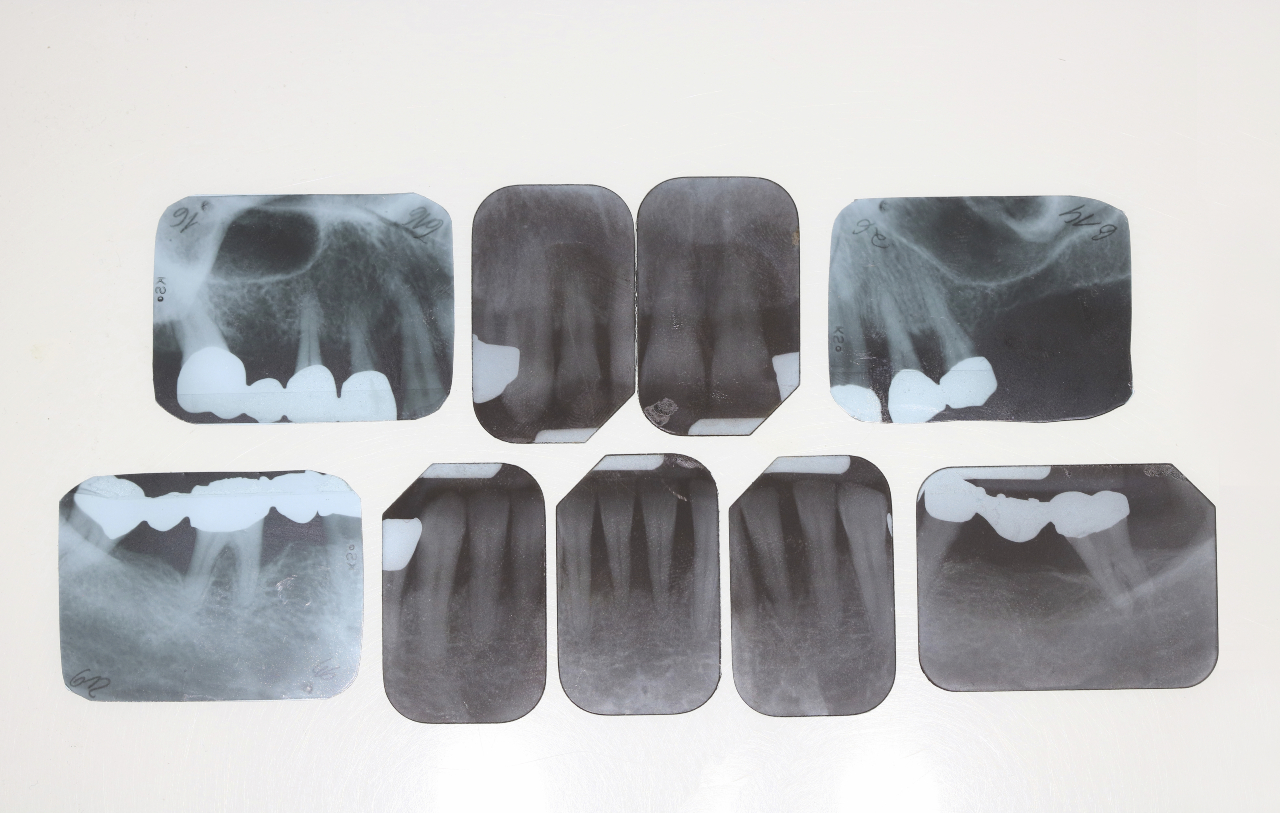

Ab dem ersten Geburtstag gilt dann: Zweimal täglich putzen mit einer reiskorngroßen Menge Zahnpasta mit Fluorid (Abb. 2). Es ist wichtig, dass die Eltern die Zahnpasta genau dosieren. Lawrenz: „Die empfohlene Zahnpastamenge darf nicht überschritten werden, um eine zu hohe Fluoridaufnahme zu vermeiden. Denn Säuglinge und Kleinkinder können Zahnpasta noch nicht ausspucken.“

Nach dem zweiten Geburtstag werden die Zähne zweimal täglich zu Hause mit einer erbsengroßen Menge Zahnpasta (Abb. 3) geputzt. Das Kind lernt das Putzen, die Eltern putzen die Kinderzähne sauber. Dazu kann ergänzend ein drittes Zähneputzen in Kindergärten und Kitas kommen.